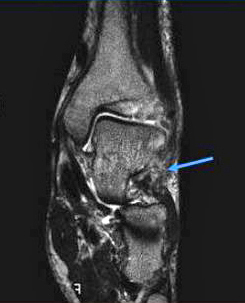

足首が腫れている2